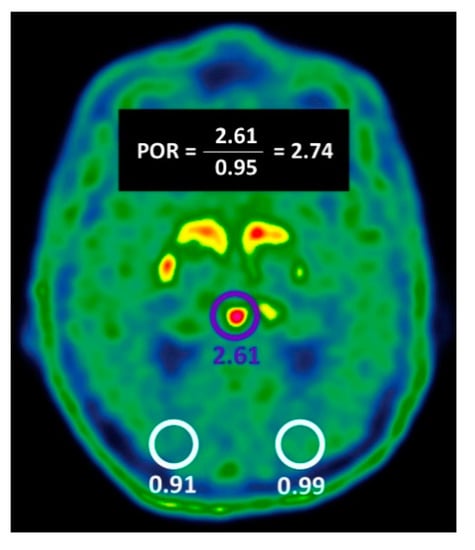

2.2. Evaluation of Pineal Body 18F-DOPA Uptake Parameters to Identify NSD

| POR ≥ 1.57 | 44/69 (63.8%) | 11/43 (25.6%) | <0.01 |

| POR ≥ 1.57 | 44/69 (63.7%) | 32/43 (74.4%) | 76/112 (67.8%) | 44/55 (80%) | 32/57 (56.1%) |

| VA-BG OR POR ≥ 1.57 | 68/69 (98.5%) | 29/43 (67.4%) | 97/112 (86.6%) | 68/82 (82.9%) | 29/30 (96.6%) |

| VA-BG AND POR ≥ 1.57 | 37/69 (53.6%) | 43/43 (100%) | 80/112 (71.4%) | 37/37 (100%) | 43/75 (57.3%) |